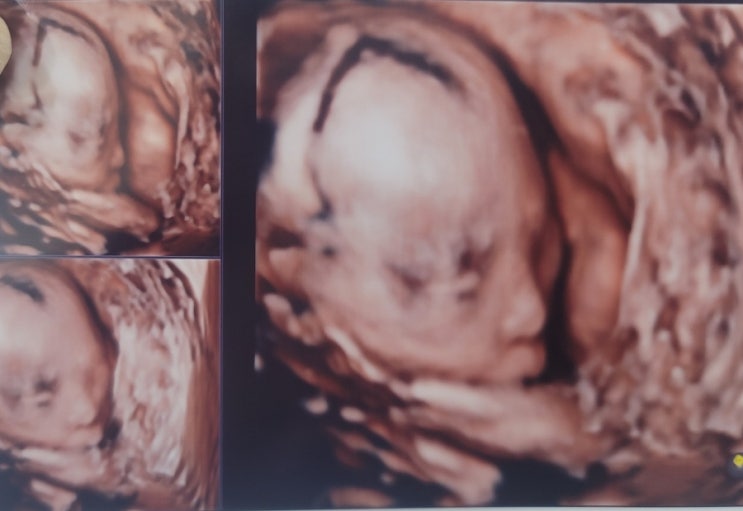

이벤트가 풍성했던 임신성공기:)

안녕하세요. 샤샤에요:) 블로그를 어떻게쓰는거더라 싶을 정도로 오랜만에 쓰네요. 그도만 엄청 마라맛 육...